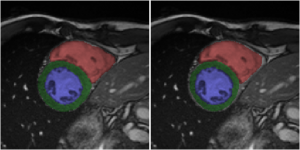

Fig. 3 shows consistent accuracy for the segmentation of all anatomies ({LV,RV,Myo} at {ED,ES}) over a large range of values for . In terms of DSC, Myo is the hardest anatomy to segment, while regarding Hausdorff distance, RV appears to be challenging because of the sensitivity of this distance measure to outliers. These results are around to worse than the best ones in the ACDC challenge [5]. However, no direct comparison can be made with the ACDC challenge results [5] as we did not obtain results on the test set because of the inference approach described in Sec. 2.4 consisting of the assessment of the six central slices per volume.

The bottom row of Fig. 3 shows the segmentation results along with their ground truth for and , where three out of twenty-five cases are misdiagnosed (we show two correct and one incorrect diagnosed case). For the case that has been incorrectly diagnosed in Fig. 3 (rightmost image, ARV misclassified as NOR), the shown under-segmented RV segmentation is representative of the entire ES phase, while for the ED phase, the RV is correctly segmented. Given that ARV relies on RV ejection fraction, such mistake in the segmentation would suggest adequate myocardial contraction and explain why this case is classified as normal. This mistake provides evidence that the features used for training the classification parameters may be strongly correlated with segmentation accuracy. The other two misclassifications involve scans that have imaging artifacts near the heart, similar to the middle image in the bottom row of Fig. 3. Interestingly, the only four cases in the validation set that contain imaging artifacts have a softmax probability (i.e., classification confidence) of around 0.7, while all other scans have a probability near 1. Segmentation performance is unaffected by such artifacts, and two of these four cases are still correctly classified, but it does show that classification performance suffers in scans with imaging artifacts.